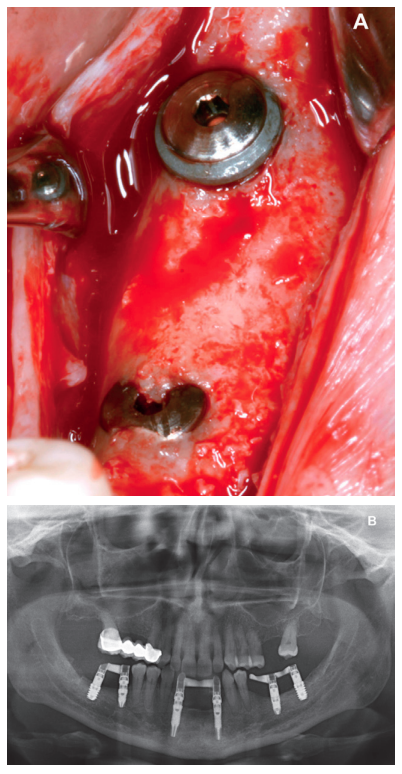

Finally, the stability of both treatments can be seen in the final X-ray at 8 years of age, where both are stable without bone loss (Figure 13).

Six months aft er the insertion of the extra-short implants, the final prosthesis was inserted; in this case, screwed and with an intermediate (transepithelial) component; just as the lower prosthesis in the third quadrant was made. At this point in ti me, the philosophy of work using a screwretained prosthesis with a transepithelial and the search for tightness and passive fi t were the dominant concerns for implant rehabilitation, and this is sti ll so today (Figure 12).

Six months after implant placement, the final prosthesis was made by using a cemented bridge. This prosthetic protocol is also not one we currently use, where tightness, sealing and the use of screw-retained prostheses using an intermediate or transepithelial component prevail. However, at that ti me, this type of rehabilitation and the conformation of a “bio” emergence profile in the abutments was how these cases were treated (Figure 8)13-18. The implementation of transepithelial implants in screw-retained prostheses opens a new horizon in the prosthesis, changing our working group protocol of towards an improvement in the implant-prosthesis seal, at the same ti me as prosthetic imbalance is reduced (due to taking the impression directly on the transepithelial and not on the implant connection) and tightness is improved; which reduces the risk of peri-implantitis, among other things19-20.